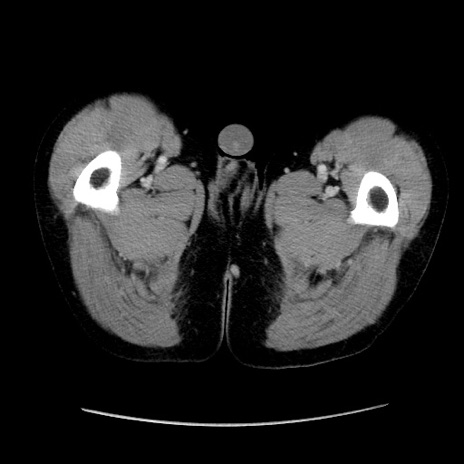

症例37(横断像)

【症例】40歳代 男性

【主訴】腹痛

【現病歴】4時間ほど前に電車に乗車中に臍部上より腹痛出現。徐々に増悪し起立困難となり、救急外来受診。生ものは数日食べていない。今朝お雑煮を食べた。

【身体所見】BT 36.8℃、BP 117/84mmHg、HR 91/min、SpO2 97%、苦悶様、腹部:臍上部広範囲圧痛あり、反跳痛±

【データ】WBC 8100、CRP 0.03